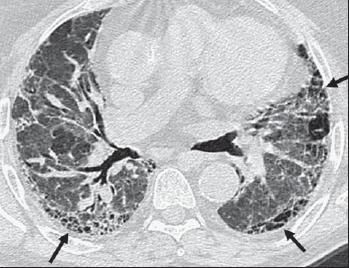

Both UIP and NSIP patterns tend to have a peripheral and basilar predominant distribution. Often, NSIP is described as having areas of subpleural sparing as opposed to the immediate subpleural fibrosis and honeycombing of UIP (Figure 3). Distinguishing UIP from NSIP radiographically can be quite difficult, even for expert radiologists; however, when the typical features of the UIP pattern are present, the ability of HRCT to help predict pathological UIP is generally quite good.25-27

Figure 3 –Nonspecific interstitial pneumonia (NSIP) was detected in a 35-year-old woman who had rheumatoid arthritis. Transverse high-resolution CT demonstrates peribronchovascular and basilar predominant distribution of ground-glass opacity with associated traction bronchiectasis (white arrows). The areas of immediate subpleural sparing (black arrows) are specific to the radiological appearance of NSIP.